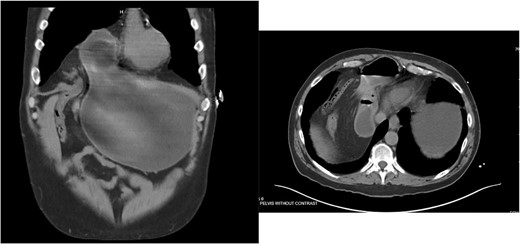

Approximately ten years prior, he had undergone coronary artery bypass surgery (CABG) with a xiphoidectomy. His symptoms at the time of the CT were right upper quadrant pain and epigastric fullness. He was referred for outpatient surgical evaluation. Shortly after the initial surgical assessment, he presented to the emergency department with gastric outlet obstruction. An abdominal CT was performed, showing a right-sided type 4 anterior diaphragmatic hernia with herniation of the antrum and pylorus causing the obstruction (Fig. 2). A loop of the transverse colon was also herniated into the thorax but without colonic obstruction.

Right-sided type 4 anterior diaphragmatic hernia with antrum and pylorus herniation.